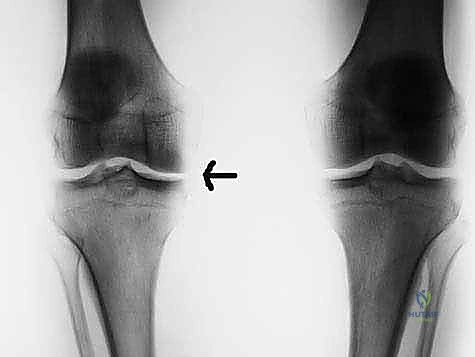

* الأشعة السينية (X-rays): بوضعيات خاصة (مثل Standing Rosenberg view) لتقييم المسافة بين العظام والتأكد من عدم وجود خشونة متقدمة، وكذلك صور الساق بالكامل (Long leg films) لقياس محور استقامة الساق.

لا يمكن زراعة أي غضروف هلالي عشوائياً. يجب أن يتطابق حجم الغضروف المزروع مع حجم الركبة الأصلية للمريض بدقة متناهية (تفاوت لا يتعدى 5%). يتم قياس عرض وطول هضبة القصبة (Tibial Plateau) باستخدام الأشعة السينية والرنين المغناطيسي، ويتم إرسال هذه القياسات إلى بنوك الأنسجة العالمية المعتمدة لتوفير طعم متطابق تماماً في الحجم والجانب (يمين أو يسار، إنسي أو وحشي).